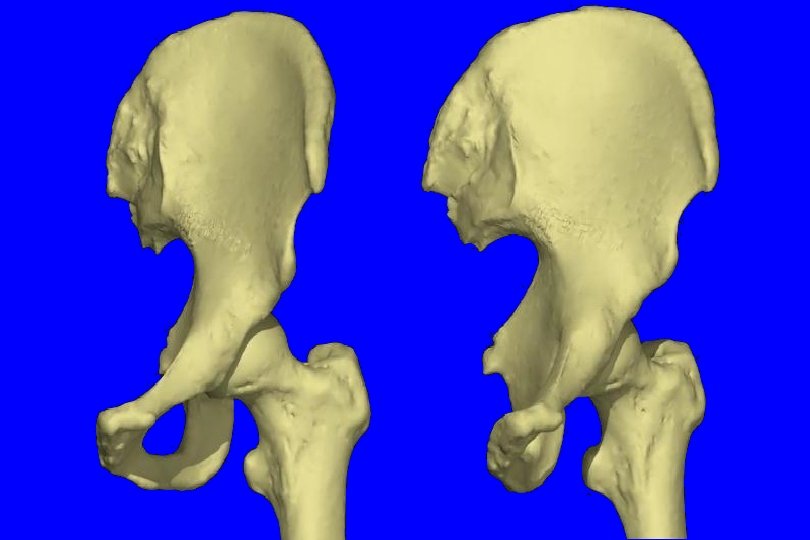

Kemik patolojileri: Asetabulum Asetabular displazi, anteversiyonda artma Ön duvar zayıf, hipoplazik, sığ Femur Koksa valga (KDA artmış) Femur başı anteversiyonu artmış